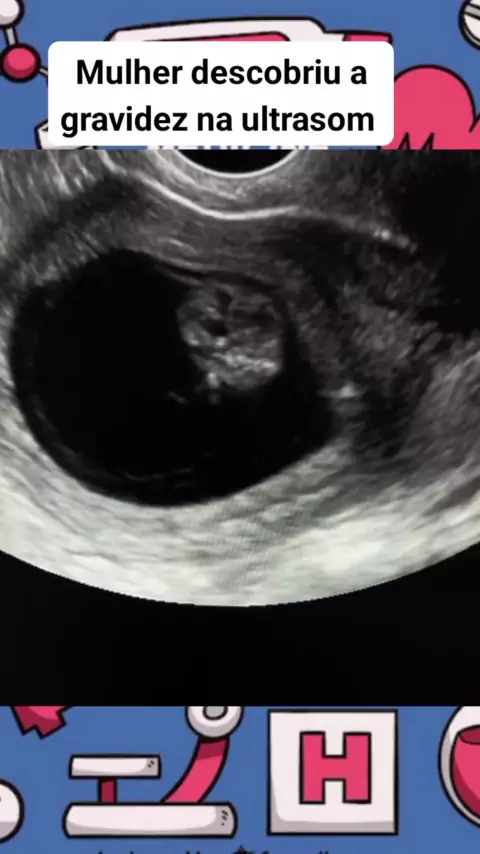

Descobriu a gravidez na ultrasom #saude #medicina #gravidez #ultrasom